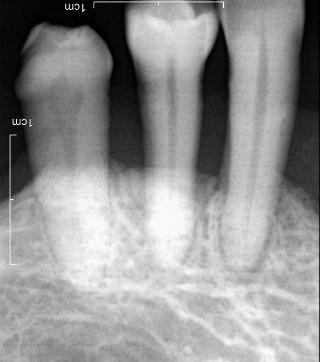

치아가 시린이유 - 마모증

안녕하세요 목동안치과의 안상우 원장입니다.여러분은 어느날 이유가 없이 치아가 시린적이 있으셨나요?치아에 이상이 없음에도 불구하고 시린증상이 있다면 마모증이 있을수 있습니다.치아의 시린증상이 생기는 현상에 대해서 알기 위해서는 치아의 구조에 대해서 알아볼 필요가 있습니다.치아는 보시는것과 같이 머리와 뿌리가 있구요.치아의 뿌리를 잇몸 안에 들어가 있습니다.치아 표면에는 법랑질이라는 단단한 조직이 있고 안쪽에는 상아질이라고 하는 상대적으로 연한 치아 조직이 있어요.이 상아질은 모세관현상에 의해서 신경에 자극을 가할수 있는 구조로 되어 있습니다.치아 안에는 신경이 들어가 있지요.결과적으로 시리다는것은 이 신경이 외부 온도변화에 의해서 자극이 되고 있다는 것입니다.치아의 옆부위가 깎이거나 쓸리는 작용에 의해서 표면이 깎여 나가게 되고 상아질이 외부로 노출이 된다면 치아 안의 신경이 외부에 가까워지면서 온도변화에 민감하게 되는것이지요.이런 증상을 마모증이라고 합니다.마모증은 우리가 직접확인을 할수도 있습니다 손톱으로 치아 옆부위를 긁어 보셔서 뭔가 걸리는것이 있다면 마모증이 있는것일 가능성이 높아요.마모증은 우선적으로 칫솔질을 잘못된 방향으로 할때 생기게 됩니다.우리가 칫솔질을 할때 보통 좌우로 하는경우가 많아요. 치약은 부드러워 보이지만 안에는 치아 표면의 이물질을 제거하기 위해서 까글까끌한 연마제가 들어 있습니다.이 마모제가 들어간 치약을 치아의 옆면을 자극하게 되면 표면이 깎여 나가면서 마모증이 생길수 있어요.이렇게 생긴 마모증은 보통 옆면이 U자형태로 나게 됩니다.또다른 원인으로는 치아에 과도한 힘이 가해지는 경우에 마모증이 생길수 있어요.우리의 치아는 매우 단단하지만 힘이 가해지게 되면 눈에 보이지 않을 정도로 매우 미세하고 휘고 있습니다.너무 강한 힘에 의해서 치아가 과도하게 휘게 되면 치아의 옆부위가 깎이면서 마모증이 발생하게 되요.이런 과도한 교합력에 의해서 생기는 마모증은 보통 도끼로 찍은 이런형태로 생기게 됩니다.또다른 원인으로는 잇몸이 내려갔을 경우에도 시린증상이 생길수 있습니다.아까 모세관 현상을 일을킬수 있는 상아질이라는 조직이 있다고 말씀드렸잖아요?치주병에 의해서 잇몸이 내려가게 되면 이 상아질의 노출범위가 넓어지게 되어 시린증상이 나타날수 있어요.시린증상을 줄이기 위해서는 이런 원인들을 제거해 줘야 합니다.우선 칫솔질로 생기는 마모증은 칫솔질을 할때 치아에 너무 강한힘을 주지 마시고 치아가 난 방향으로 약한힘으로 칫솔질을 해야 합니다. 일단 마모증이 생기게 되면 해당부위가 재생되거나 하지 않기 때문에 시린증상으로 인해서 불편감이 있다면 치과재료로 충전을 해줄수 있어요또한 힘에 의해서 생기는 도끼 형태의 마모증은 치아에 가해지는 힘을 줄여야 합니다.지속적으로 치아에 과도한 힘이 가해지다보면 이런마모증이 심해지다가 결과적으로 치아가 부러지는 현상이 발생할수 있어요.마지막으로 잇몸이 내려가서 생기는 시린증상입니다.치아를 둘러쌓고 있는 잇몸이 없어지게 되어 치아 뿌리가 드러나게 되면 치아가 시릴수 있어요. 제일 좋은것은 잇몸이 내려가지 않는것이 좋지만 염증이나 그외의 원인으로 잇몸이 내려가서 시리게 되었다면 치아표면을 코팅하는 약제를 이용하여 시린증상을 완화할수 있습니다.마모로 인해서 시린치아의 치료방법은 아까 말씀드린것처럼 마모가 된 부위를 충전해 주는것입니다.치아를 충전하는 재료에는 레진이라는 재료와 GI라고 하는 재료가 있어요.레진이라는 재료는 보험적용이 되지 않아서 충전시에 비용이 조금비쌉니다. 하지만 색상이 치아와 거의비슷하고 강도가 좋아요. 레진은 비보험 진료기 때문에 병원마다 비용에 차이가 있을수 있는데 치아 하나를 치료하는데 보통 8~12만원정도 합니다.GI라고 하는 글래스아이오노머라고 하는 보험이 적옹되는 재료도 있는데요이재료는 레진보다 색상이 조금 밝고 강도가 약하긴 하지만 보험적용이 되기 때문에 약 8천원정도의 비용으로 치료를 할수 있습니다.잇몸이 내려가서 시린 치아는 잇몸의 염증을 줄이도록 해야 하고 뿌리가 드러난 부분은 치과용 약제를 도포해서 시린증상을 줄일수 있습니다치아가 시리다면 시린원인을 제거해 줘야 합니다.칫솔질이나 과도한 힘같은것 말이죠.또한 잇몸이 내려가는것을 방지해서 치아의 뿌리가 노출되지 않도록 하는것이 좋습니다.또한 마모된부위는 치과용재료로 충전을 해서 시린증상을 줄이는방법도 있어요.올바른 칫솔질과 관리로 마모증이 생기지 않도록 해준다면 치아가 시린증상을 예방할수 있습니다.치아관리 잘 하셔서 꼭 마모증이 생기지 않도록 해주세요.